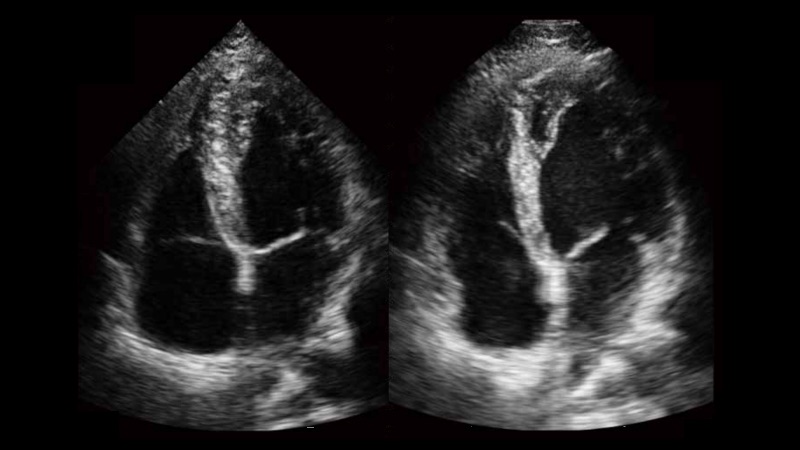

新一代微米成像技術大大提高了器官和病變的可見性。高清對比度分辨率將抑制斑點噪聲,同時保持真實的組織結構。

自動識別收縮和舒張末期心肌內膜,自動計算射血分數EF值。